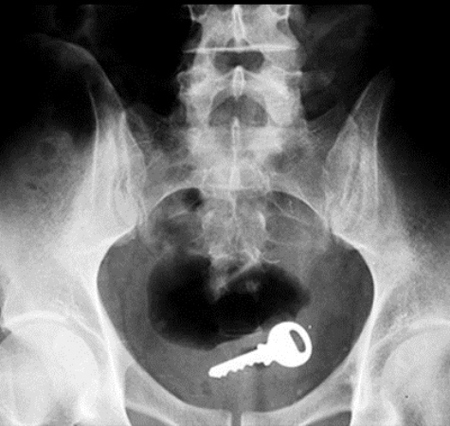

มาดูภาพเอกซเรย์ สารพัดสิ่งของที่เคยหลุดเข้าทวารหนัก

เผยภาพเอกซเรย์สุดอึ้ง สารพัดสิ่งที่เคยหลุดเข้าไปภายในทวารหนักผู้ป่วยทั่วโลก แปลกพิสดารกันจริง ๆ

การยัดสิ่งของต่าง ๆ เข้าไปในทวารหนักนั้น ไม่ว่าจะด้วยเหตุผลเพื่อหลบซ่อนการตรวจของเจ้าหน้าที่ทางการ หรือเป็นความผิดพลาดจากการแก้ขัดเมื่อเกิดอารมณ์ทางเพศก็ตาม สิ่งของที่หลุดเข้าไปนั้นล้วนแล้วแต่สร้างอันตรายให้กับอวัยวะภายในของผู้ป่วยได้หมด แต่ถึงจะเป็นอย่างนั้น เคสทางการแพทย์ว่าด้วยเรื่องของสิ่งแปลกปลอมที่หลุดเข้าไปในทวารหนักก็ยังมีให้เห็นอยู่เรื่อย ๆ ถมเถ แต่ละอย่างทำเอาอึ้ง ทึ่ง แบบไม่คิดว่ามันจะหลุดเข้าไปในทวารหนักได้จริง ๆ ดังเช่นตัวอย่างเคสที่เรานำมาฝากกันในวันนี้..

กุญแจ